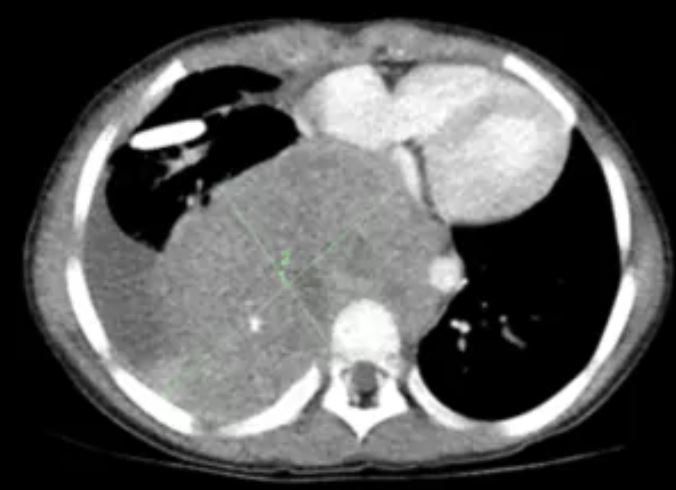

O neuroblastoma é o terceiro tipo de câncer infantil mais recorrente, representando de 8% a 10% de todos os tumores infantis. A estimativa é que que apareçam, por ano, 387 novos casos no Brasil. Metade deles classificados como de alto risco.